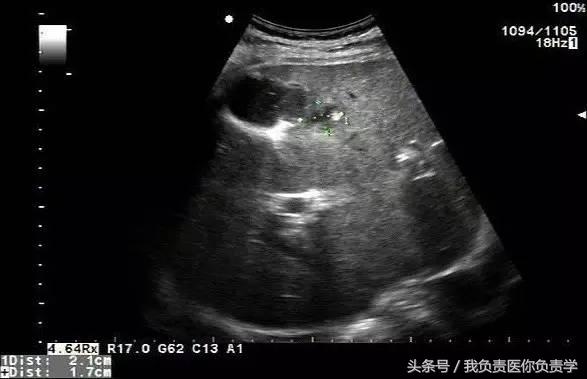

典型病例 1

患者男,64岁,因右上腹疼痛半月余就诊。查体发现右上腹部轻压痛,无发热。超声检查所见如下:

图1示胆囊增大,囊壁增厚,囊内透声差

图2示于胆囊外侧可见一局限性囊性无回声区

图3示胆囊与囊性回声区间隐约可见裂隙相通

图4和5为局部放大图像,可见胆囊与囊性回声区间可见直径约2mm的通道

超声检查考虑为胆囊炎合并胆囊穿孔,后经CT检查证实。